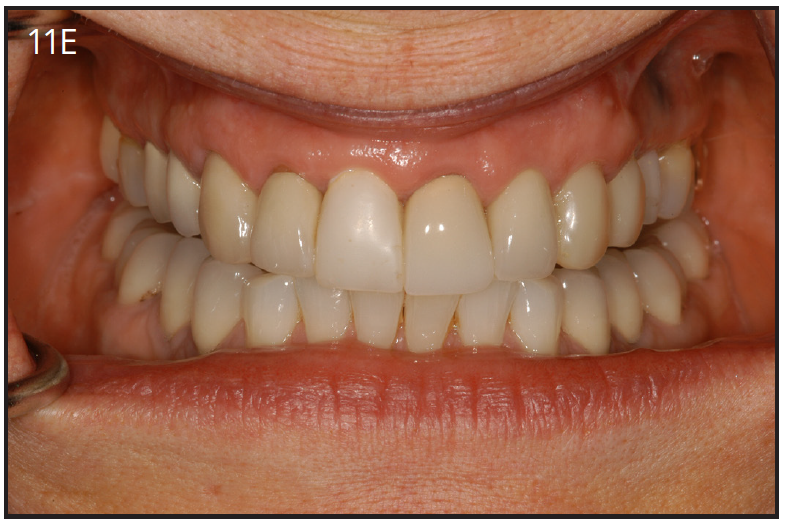

An implant most closely replicates the feel of a natural tooth. Once it is osseointegrated, many patients cannot differentiate an implant from a natural tooth. Furthermore, dental implants do not decay or need a root canal. Even though the cost is slightly more than a bridge, it is a great investment for the future, as implants usually last longer than a bridge. A 10-year report on posterior single implants shows a success rate of 97%.29 Once an implant is placed, an integration/healing time of approximately 4 months is necessary before final crown is placed. A temporary crown can be placed the same day the implant is placed. (Figures 11A-E)

Figure 11E – Four months post surgery with temporary crown over

implant at #8